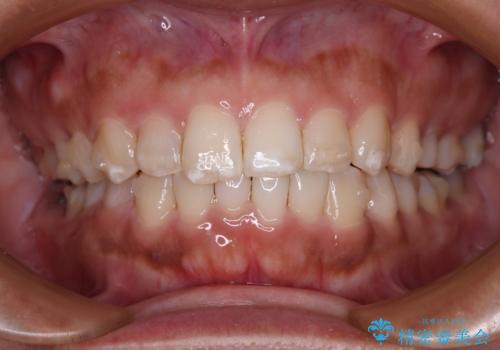

- 上下前歯の叢生を気にして来院された患者様です。

軽度な叢生であり、安価で短期間の治療を規模されていたため、インビザライン・モデレートを用いて矯正治療を行うこととしました。